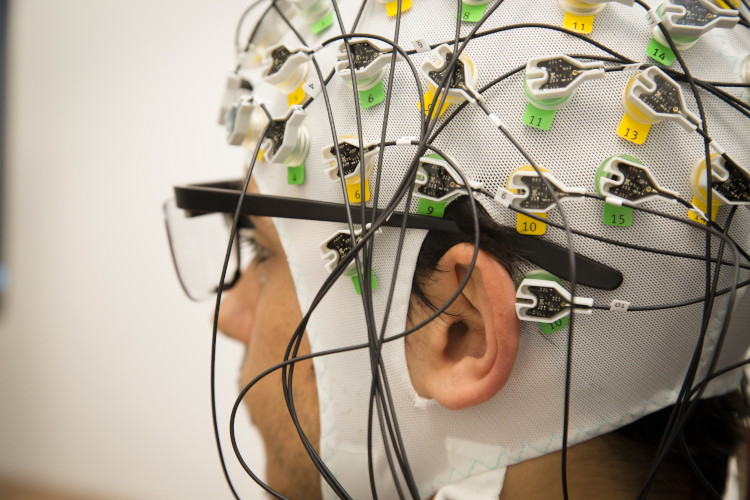

Center for Synaptic Neuroscience and Technology

Università di Genova, Genova

Il Center for Synaptic Neuroscience and Technology (NSYN) applica un approccio multidisciplinare allo studio delle funzioni cerebrali e alle patologie correlate. Lo scopo è sviluppare tecnologie innovative applicabili nell'ambito delle neuroscienze.